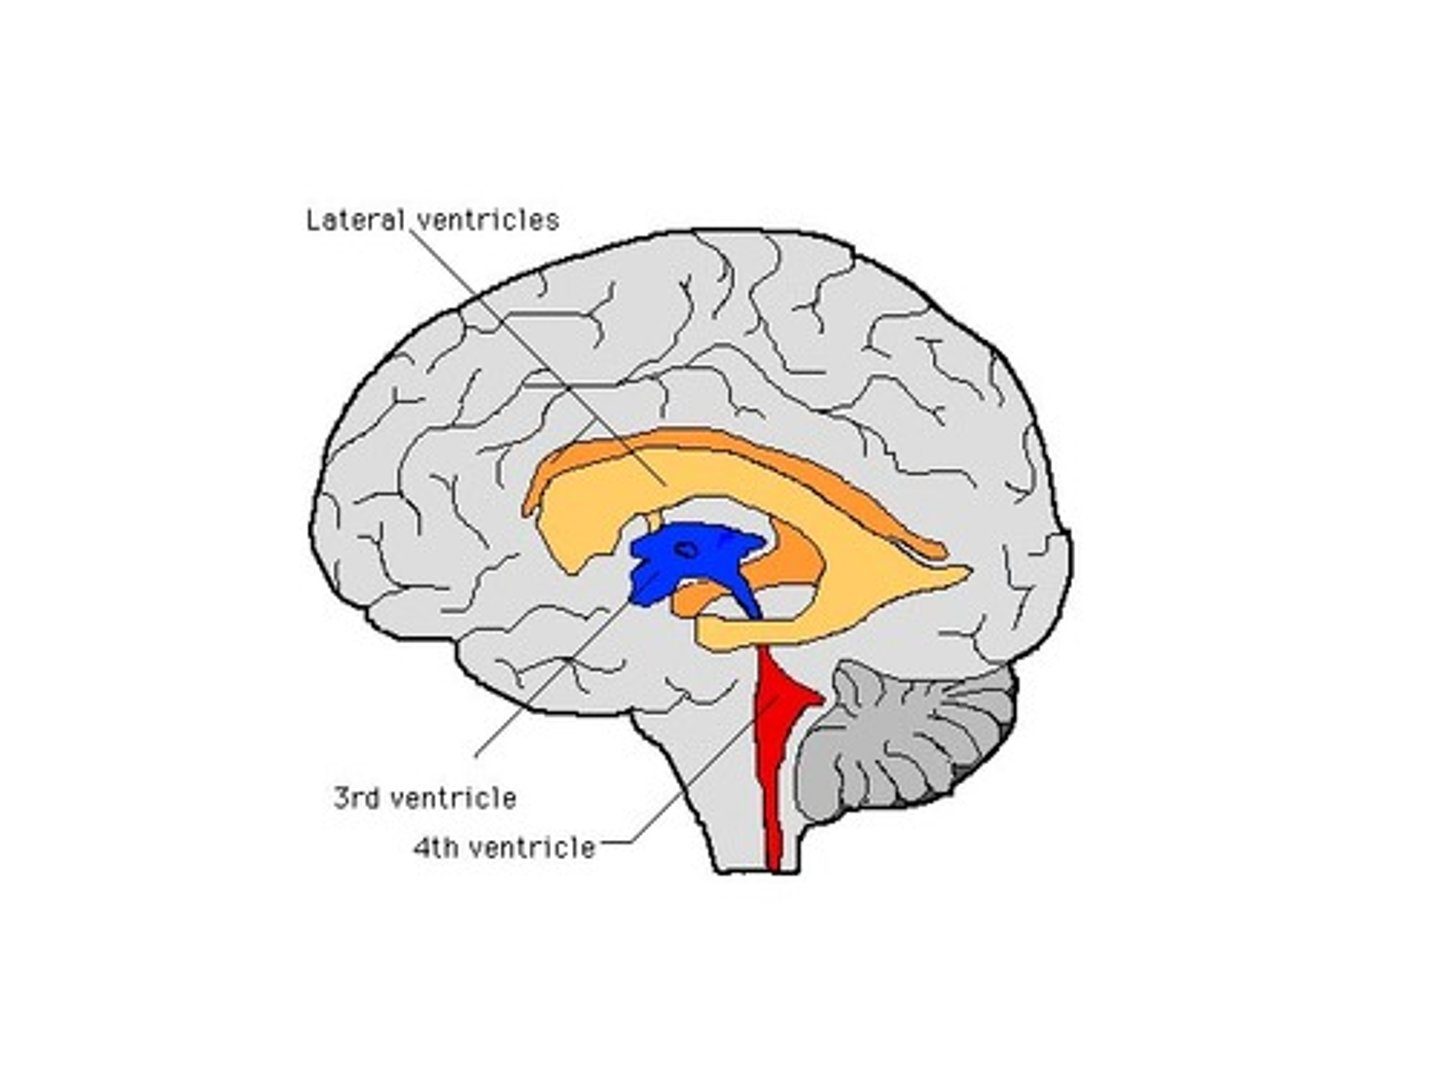

What is ‘closed’ vs ‘open’ medulla referring to?

The "open" medulla is where the fourth ventricle opens, forming the dorsal surface, while the "closed" medulla is where the fourth ventricle is surrounded by the medulla, and the central canal is still enclosed.

lateral ventricles

3rd ventricle

4th ventricle